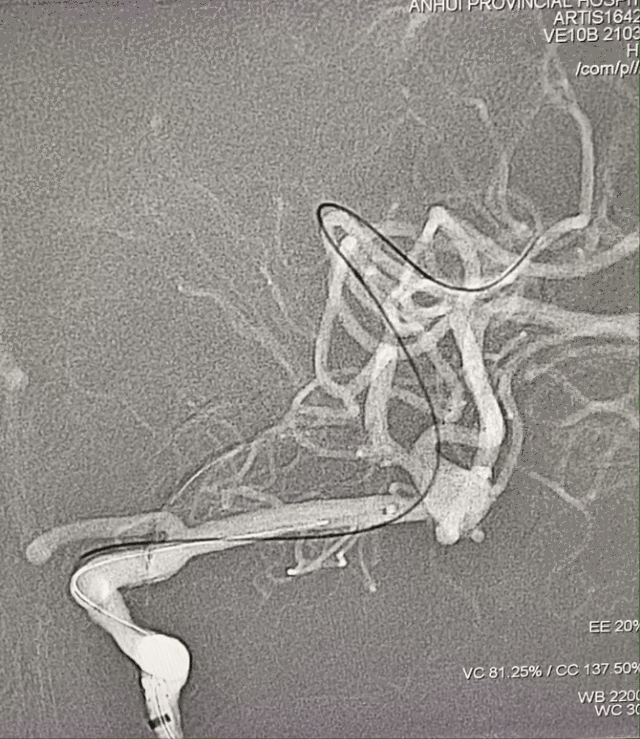

脑血管造影

DSA:右侧大脑中动脉瘤,形态不规则,夹层可能,瘤体可见分支血管,4.5mm×3.2mm,瘤颈5.8mm;远近端载瘤动脉直径分别为2.71mm、2.93mm。